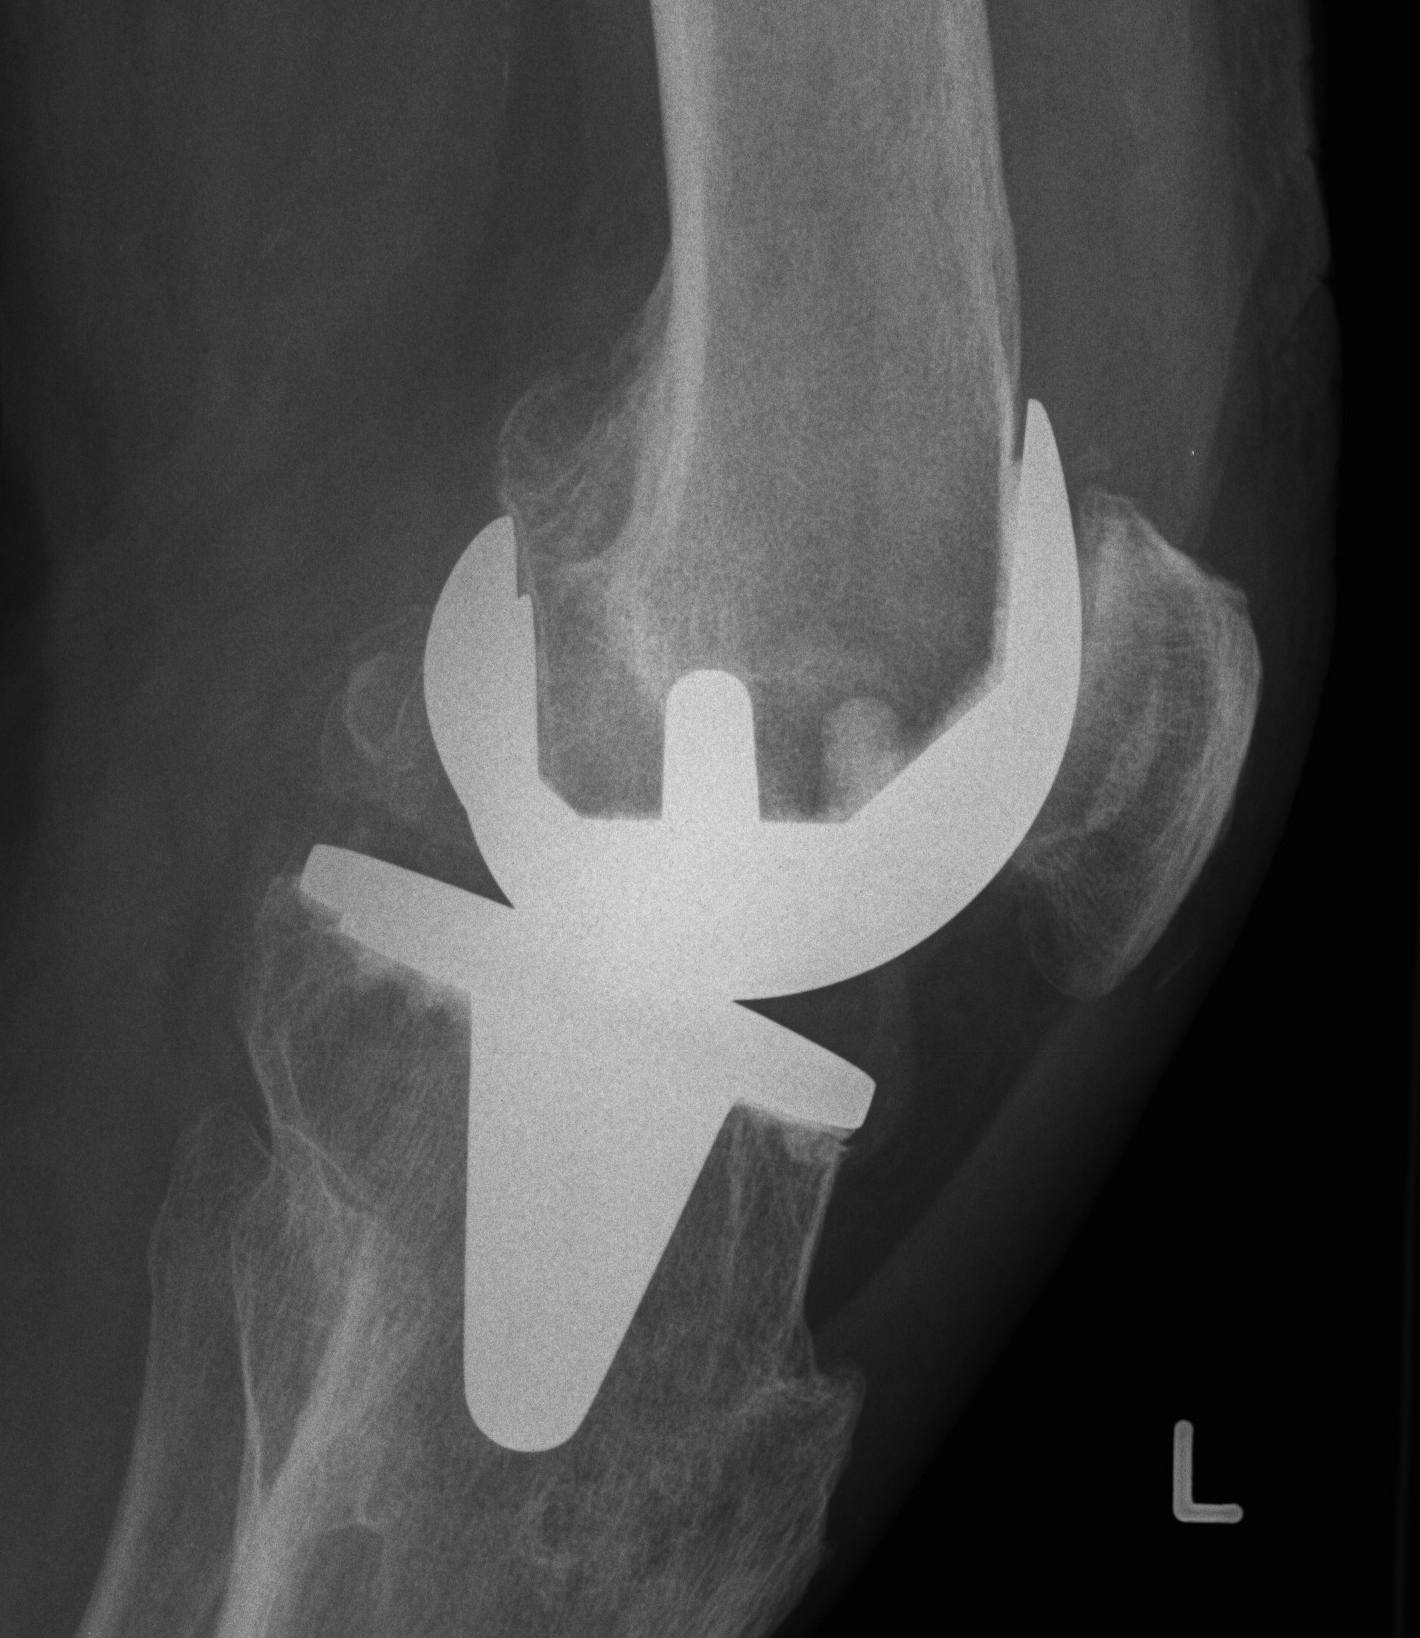

AP instability

A. Loose in flexion

Issue

- can get knee dislocation / post jump

Cause

- excessive posterior femoral resection

- PCL failure

A. Excessive posterior femoral resection

Revise femur

- posterior femoral augments + stem

B. Failure of PCL in CR knee

Revision femur and poly

- insert PS femur and poly

- need to have CCK revision equipment available